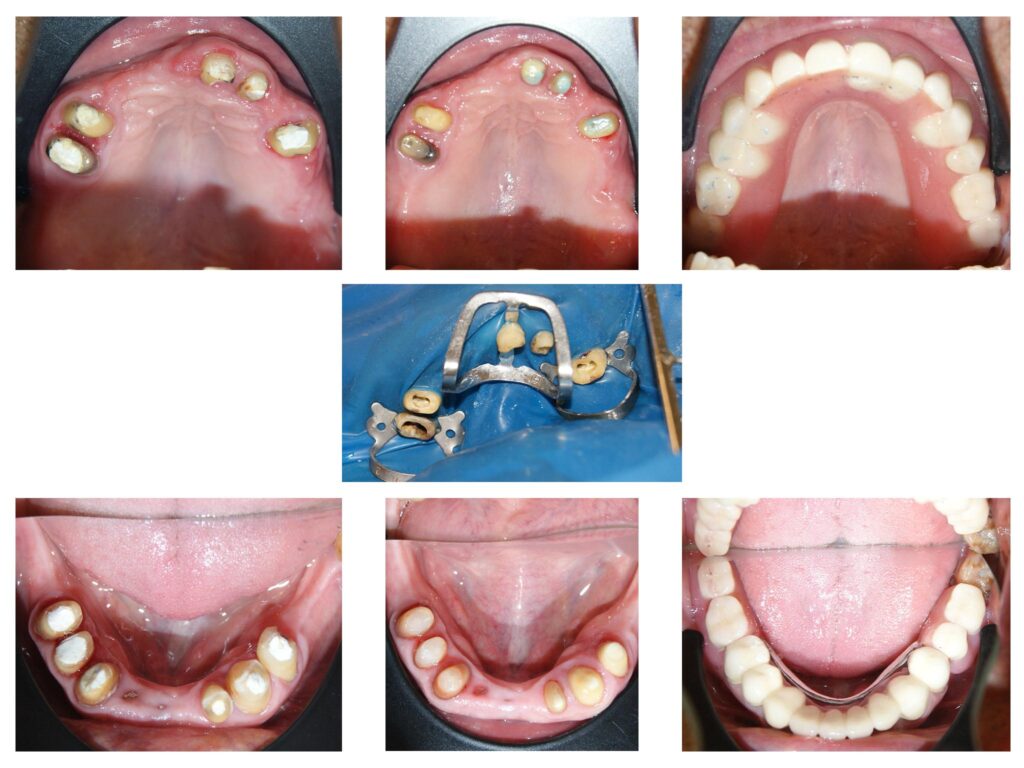

Aparatele ortodontice se aplică doar pe dinții curățați în prealabil. Cariile și resturile radiculare irecuperabile trebuie asanate după cum se vede aici